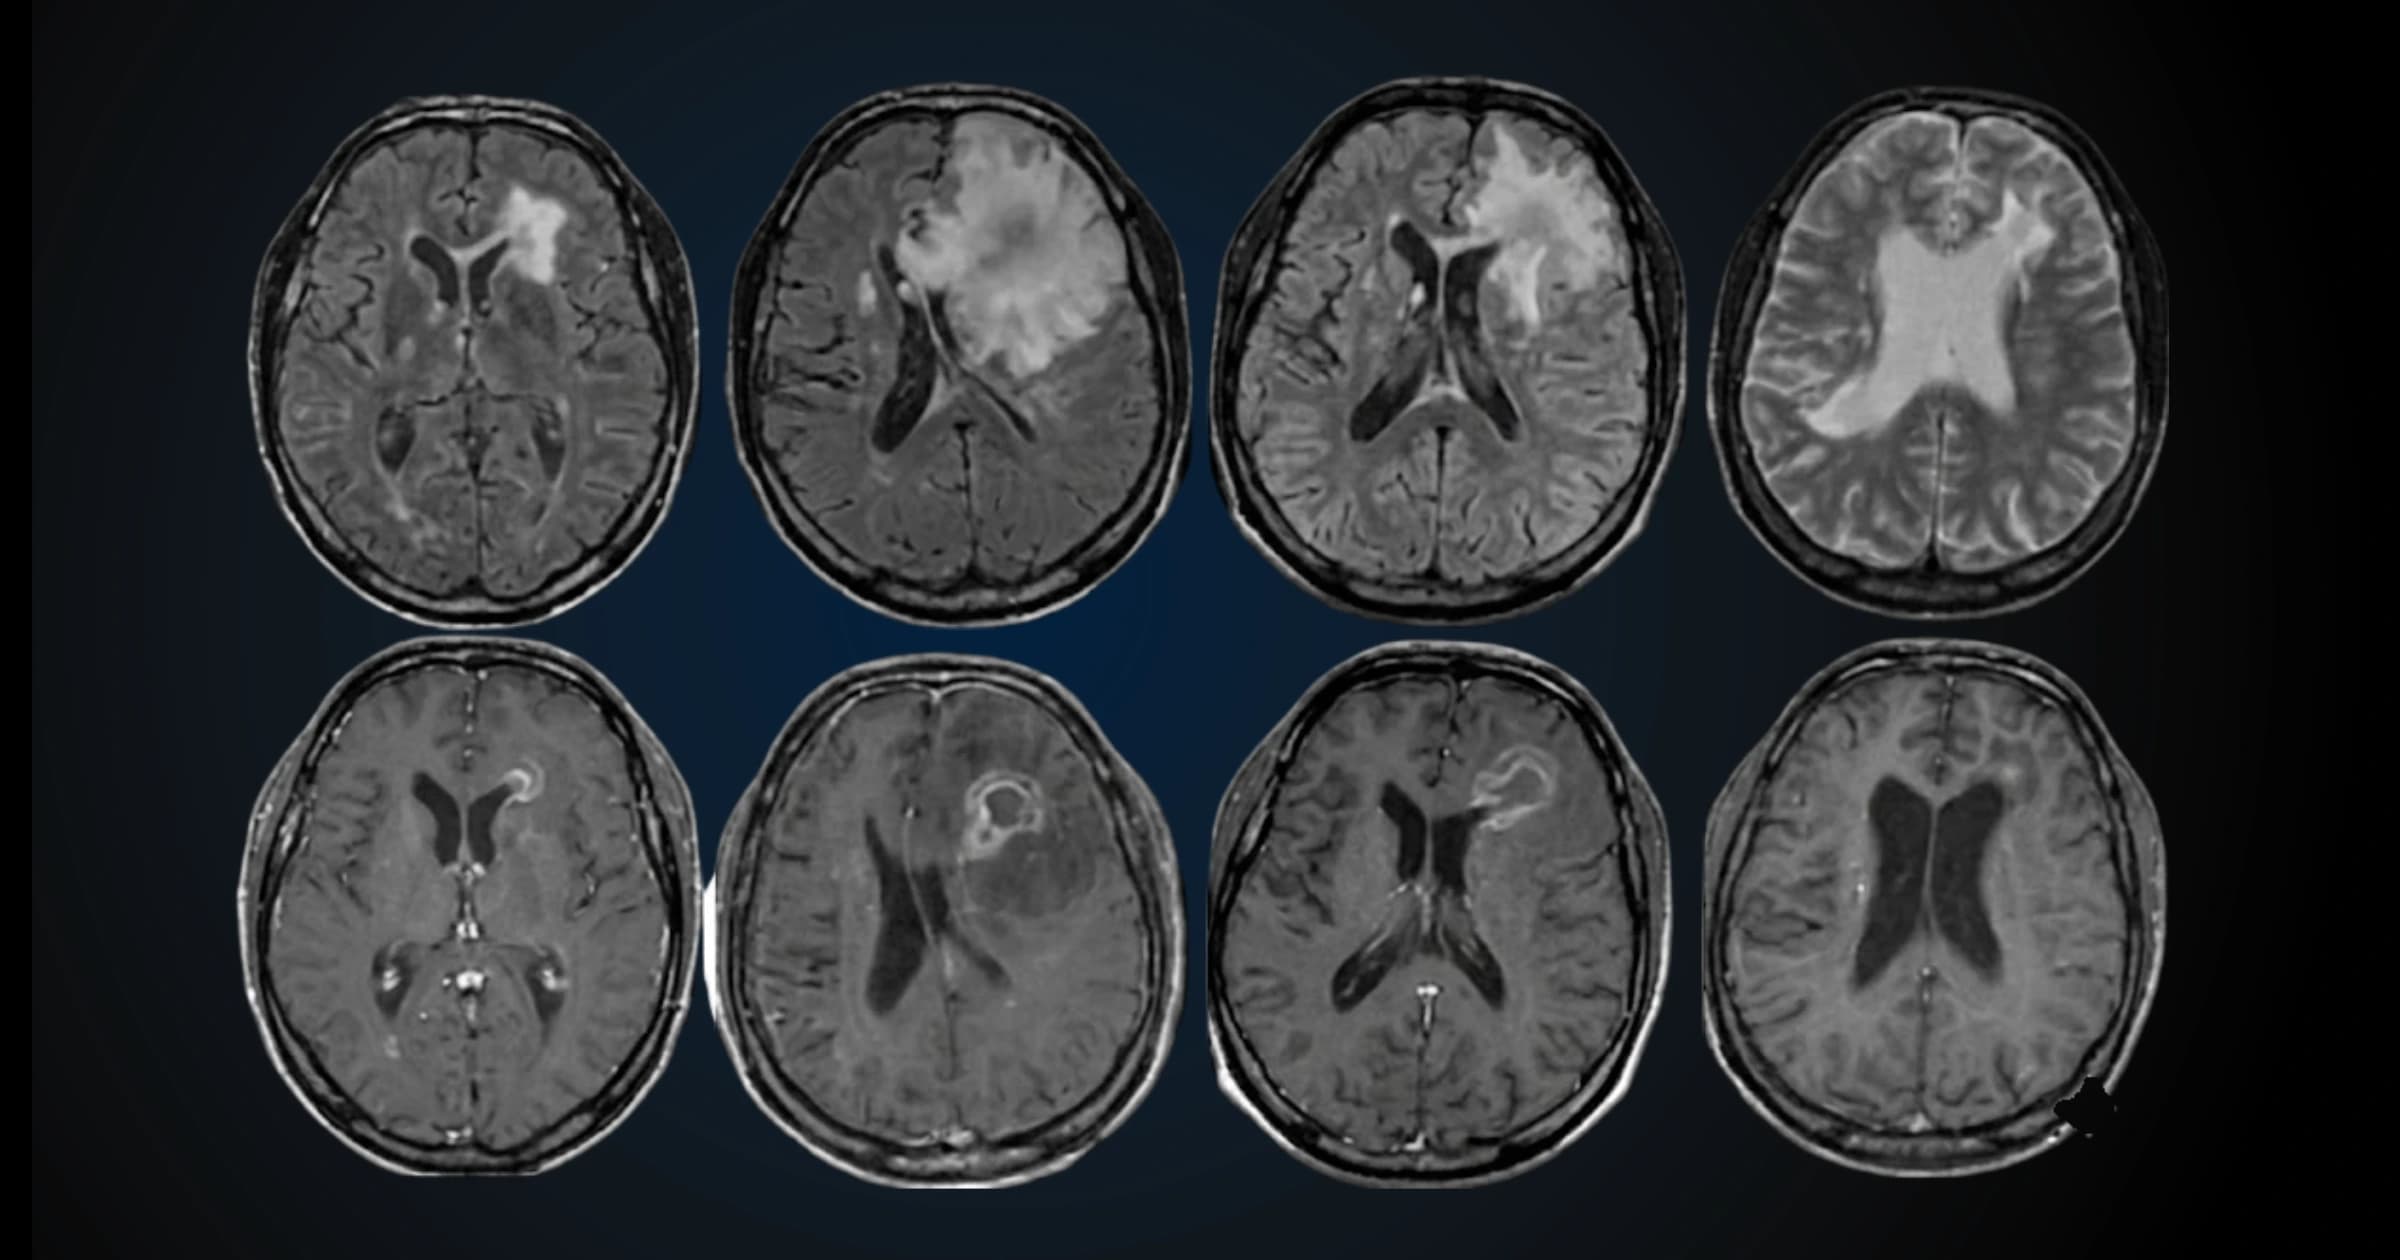

How We Detect Alzheimer's: From Brain Scans to Blood Tests

For decades, Alzheimer's diagnosis relied on clinical examination and basic structural brain imaging to rule out other causes like tumors or strokes. By the time brain shrinkage showed up clearly on conventional scans, significant damage had already occurred.

Advanced imaging techniques are changing this paradigm.

MRI-Based Volumetric Analysis

MRI-based volumetric analysis measures the volume of specific brain structures, particularly the hippocampus. Automated software like NeuroQuant performs this analysis by segmenting the brain into over 50 regions and comparing their volumes to normative data from healthy people of the same age.

Studies demonstrate that NeuroQuant's hippocampal measurements achieve 80% accuracy in distinguishing dementia from non-dementia – substantially better than visual rating by radiologists, which achieved only 69% accuracy. The software detected hippocampal atrophy in over 90% of patients while expert neuroradiologists identified it in only about 12% when relying on visual assessment alone.

The advantage is consistency. The same brain scan analyzed twice produces identical results, unlike human interpretation which can vary between doctors or even when the same doctor reviews it at different times.

However, limitations exist. NeuroQuant alone doesn't diagnose Alzheimer's – it's one piece of diagnostic evidence. It excels at measuring hippocampal and temporal lobe volumes but is less accurate for posterior brain regions. And while it detects atrophy well, atrophy can occur in other conditions besides Alzheimer's.

Advanced MRI Techniques

Newer MRI techniques can detect Alzheimer's-related damage before tissue shrinkage becomes visible. One approach uses quantitative Gradient Echo MRI to identify "dark matter" zones where neurons have died but tissue hasn't yet shrunk. These regions show up in people who test positive for amyloid but don't have symptoms yet, and they expand as disease progresses. The technique takes just six minutes and works on standard MRI machines already in hospitals worldwide.

PET Scans: The Gold Standard

PET scans remain the gold standard for visualizing Alzheimer's pathology. Amyloid PET scans directly image beta-amyloid plaques, detecting them years before symptoms appear. Tau PET scans visualize the location and extent of tau tangles. PET accuracy for detecting Alzheimer's exceeds 95% when combined with structural MRI.

The limitation is accessibility. PET scans are expensive, require radioactive tracers, and aren't widely available for routine screening. MRI offers a more accessible alternative for initial evaluation, with PET reserved for cases requiring definitive confirmation.